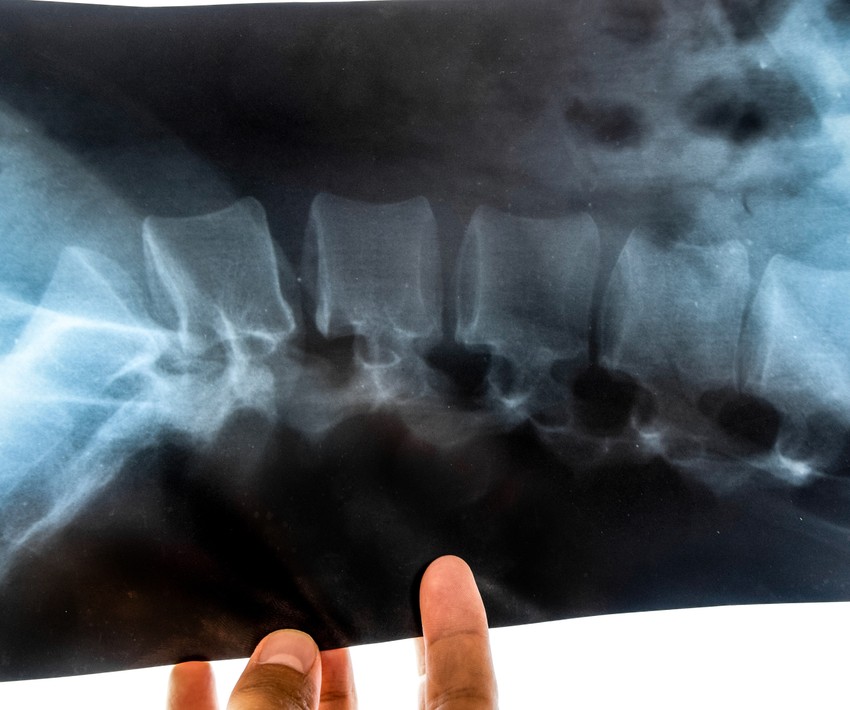

A Bechterew-kór diagnózisának legfontosabb eleme a radiológiai vizsgálat (gerincröntgen, CT, MRI). A hajlamosító HLAB27 antigén jelenléte vérvizsgálattal igazolható. A további diagnosztikus eljárások a kísérőjelenségek kimutatását célozzák (mellkasröntgen, EKG, szemészeti, nefrológiai, ideggyógyászati, stb. vizsgálat).

A Bechterew-kór (Spondylitis Ankylopoetica - SpA) egy krónikus, autoimmun gyulladásos betegség, amely elsősorban a gerinc ízületeit, a keresztcsontot, valamint a bordák és a csigolyák közötti ízületeket érinti, az elcsontosodás és a gerinc elmerevedése révén súlyos mozgáskorlátozottságot okozva, gyakran "botmerev gerinc" kialakulásához vezet, férfiaknál gyakoribb, és 20-40 éves kor között kezdődik, de ma már gyógytornával és biológiai terápiákkal jól kezelhető, az életminőség javítható.